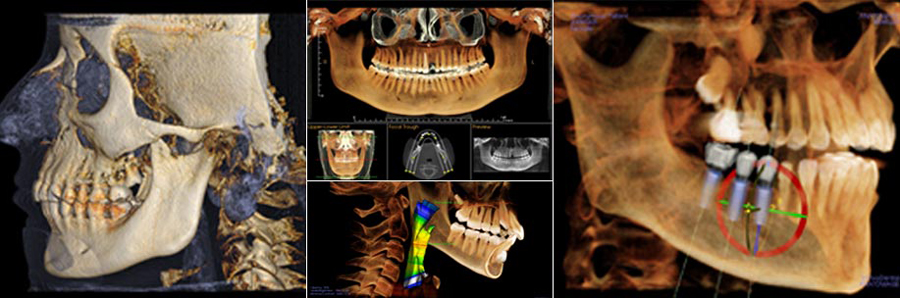

Future Smiles Orthodontics is proud to announce Guam’s first i-CAT CBCT imaging machine. This state-of-the-art technology and software are provided by i-CAT and Anatomage, the world leaders in 3D imaging for orthodontics. They have recently announced tech support for the western Pacific, and Dr. Paul is happy to announce that this will be incorporated into his services. Not only is this technology top of the line, it leads the pack on diagnosing and screening for potential tooth impactions, jaw irregularities, and sleep apnea. Patients love it because it looks like an awesome video game, but also because it more clearly diagnoses their problem areas and makes treatment even faster!

A low radiation alternative to normal CT scans, ENT specialists can use it for evaluating sinuses, tonsillar tissue, etc. and evaluate where issues can arise in allowing people to breathe more comfortably.

Sleep medicine doctors can take advantage of airway imaging and measurement and administer the appropriate treatment. When sleep apnea is addressed, a patient can get more oxygen during rest which translates to increased energy, mental alertness, and less stresses across other areas of the body. Young patients have reported improved performance in school and other activities when the orthodontist or sleep medicine doctor addresses this.

Chiropractors can visualize the cervical spine as well and assess neck alignment in all three dimensions. We are proud to serve all our local health care professionals interested in this technology and we’ll be happy to accommodate their patients for imaging services.